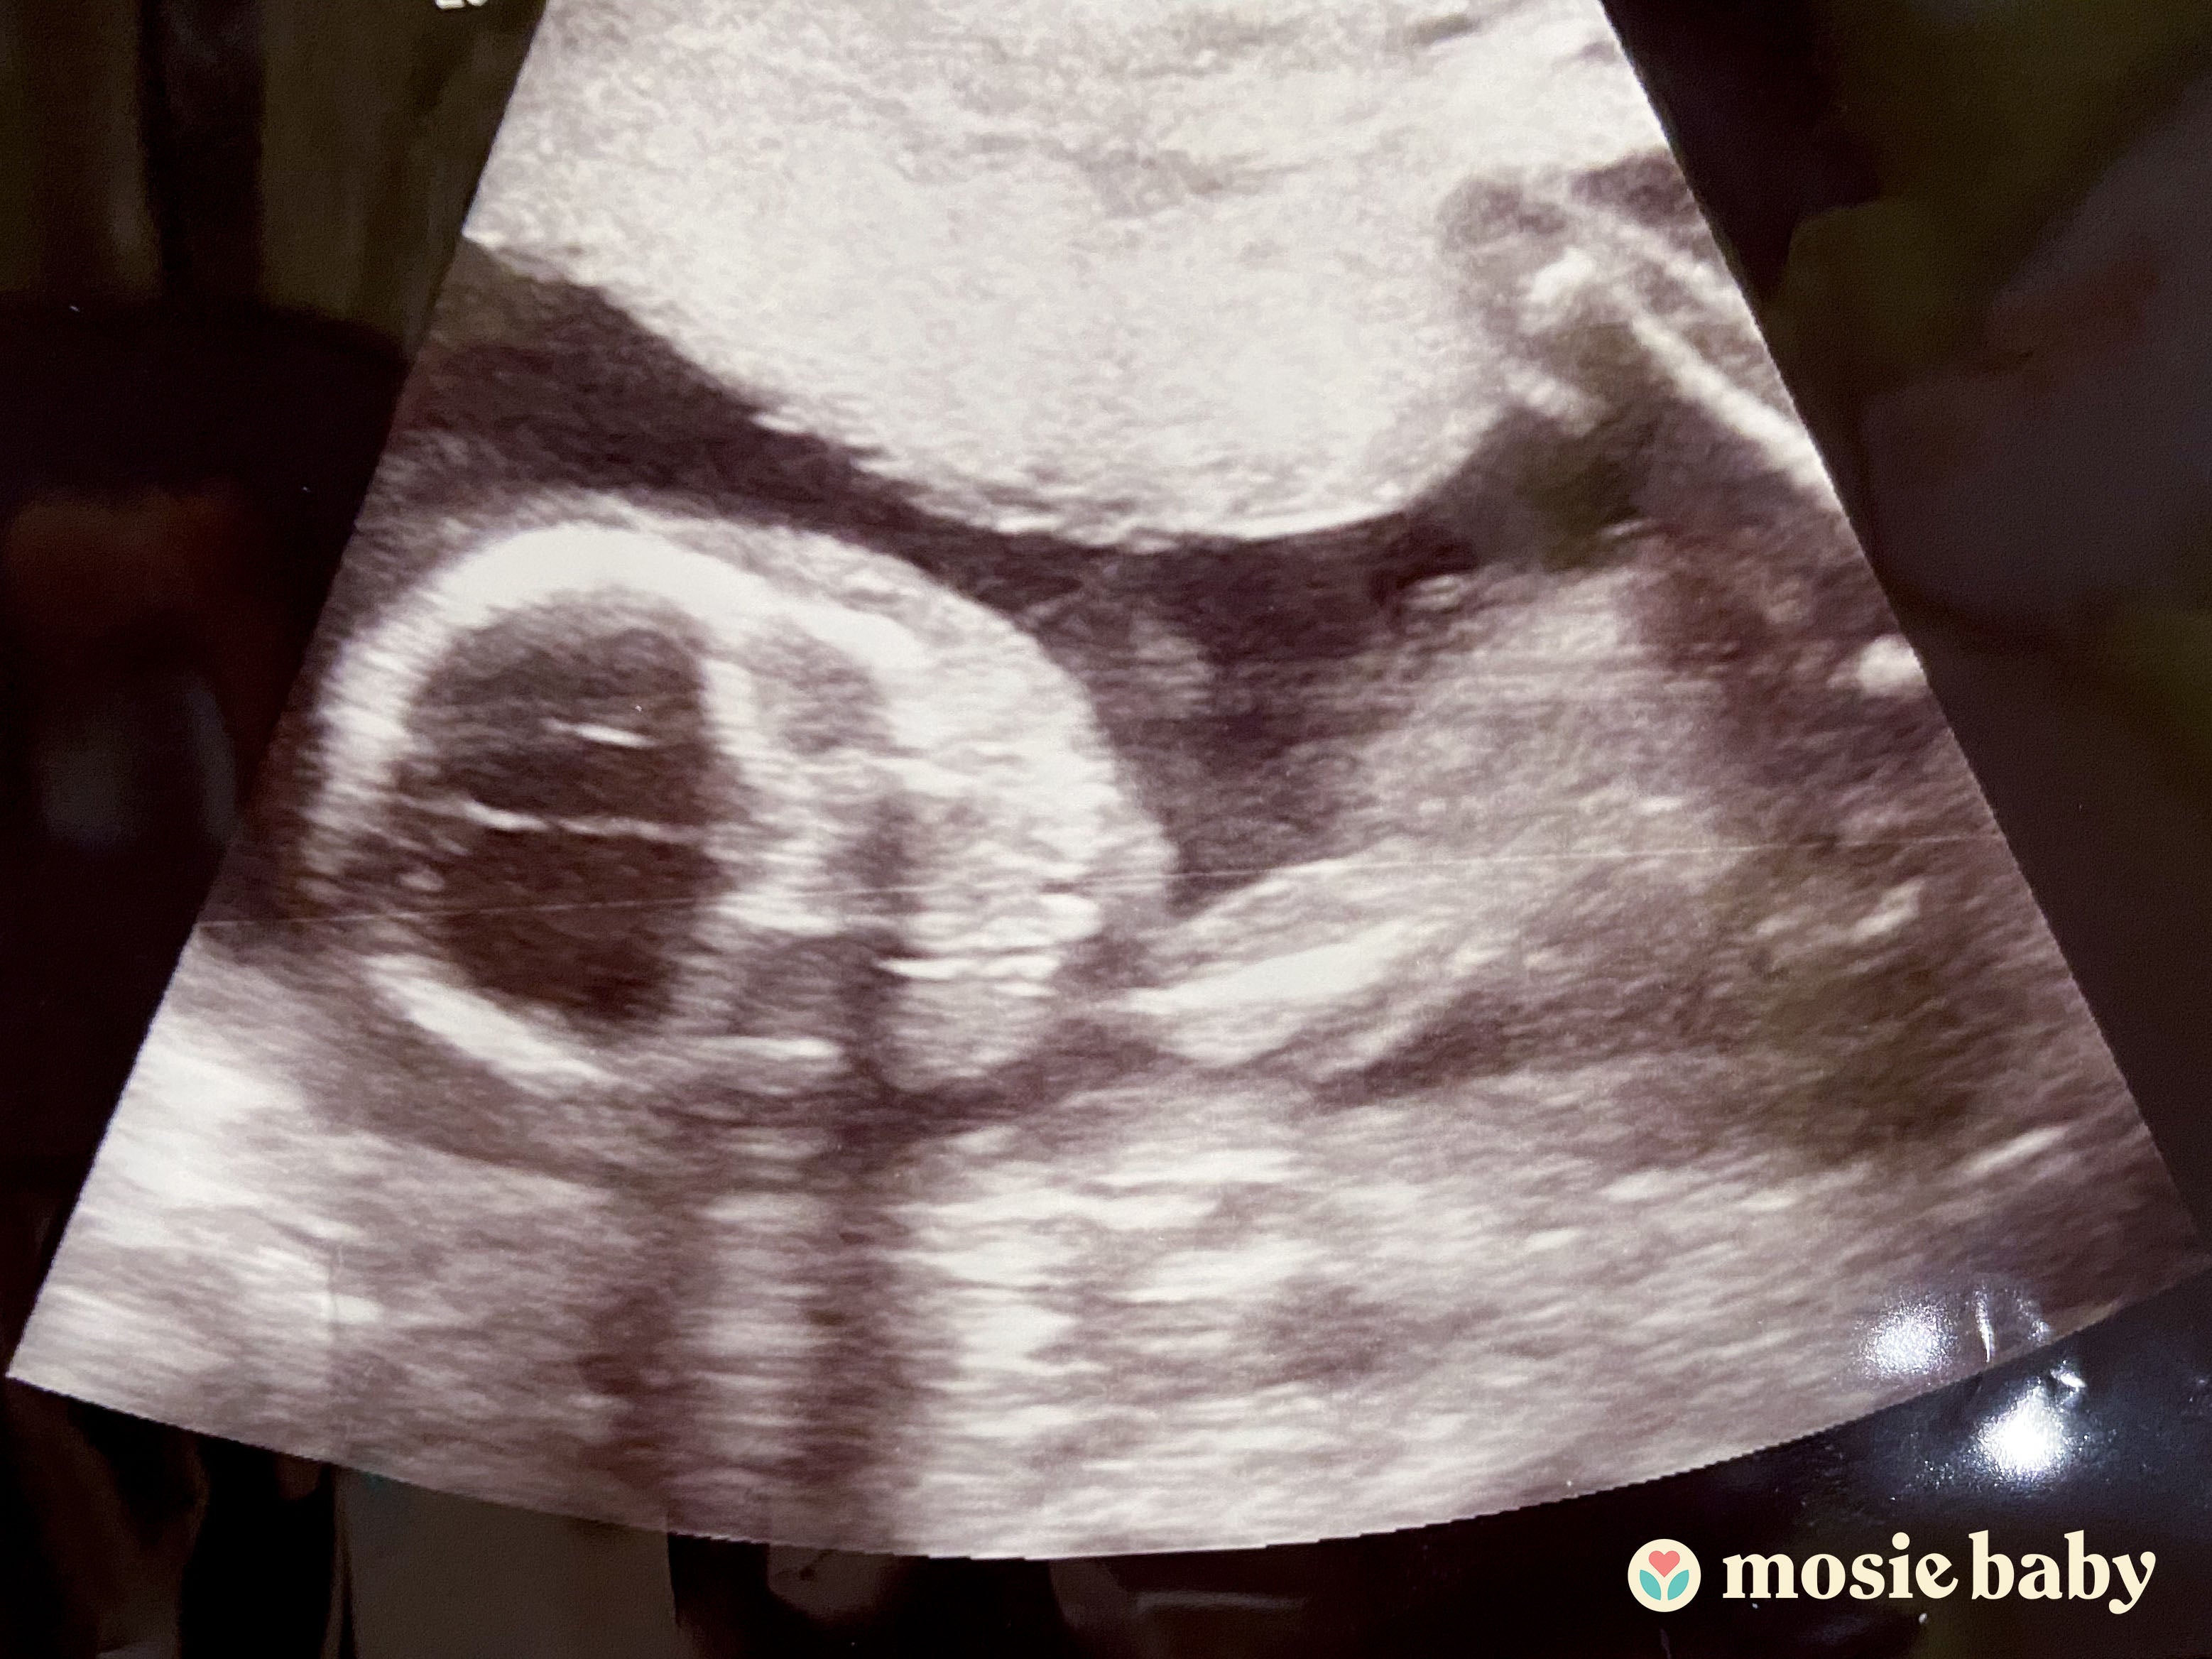

The following week after trying with Mosie Baby, I was feeling happy just because I was able to use it successfully the first time without any pain or fear. So we ordered more kits and planned to use them for a couple months. However, we never had to use the new arrived kits as after three weeks, I missed my period date and guess what...I was pregnant. I am not able to express how I felt looking at those two lines. It took me nine more pregnancy test kit purchases to be convinced that I was actually pregnant. 🥰 I booked my doctor’s appointment and he was so surprised as he was not aware about Mosie Baby. He is the best doctor I could have ever imagined for me. So thankful to him keeping patience with me and blessed to have Mosie in my hand from you guys. Never ever imagined that one try with Mosie Baby was all it would take. My doctor said, I am going to let all my other patients know about it who are planning for IUI to give Mosie Baby a try. So, once again, thank you so much to you who invented this and your entire team who made it possible to deliver in my hand safely and on time.